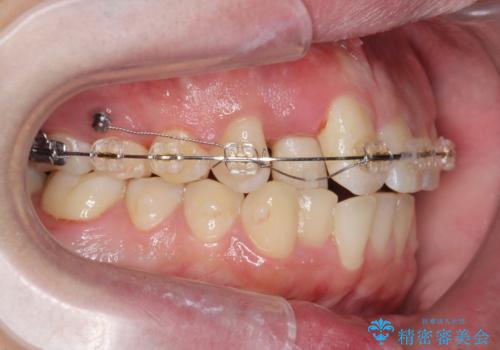

正中過剰埋伏歯で生じた前歯の審美障害 矯正治療での改善

- ワイヤー矯正 → インビザライン

- 前歯の見た目に悩まれて来院されました。

当初他院では、抜歯を行いセラミックブリッジを提案されていましたが、他の方法はないかと総合歯科治療を行う当院へと相談来院されました。

「時間がかかっても良いので、できれば歯を抜かずに矯正治療で治したい。」という強い希望があったので、矯正治療で歯並び・審美性の改善を計画します。